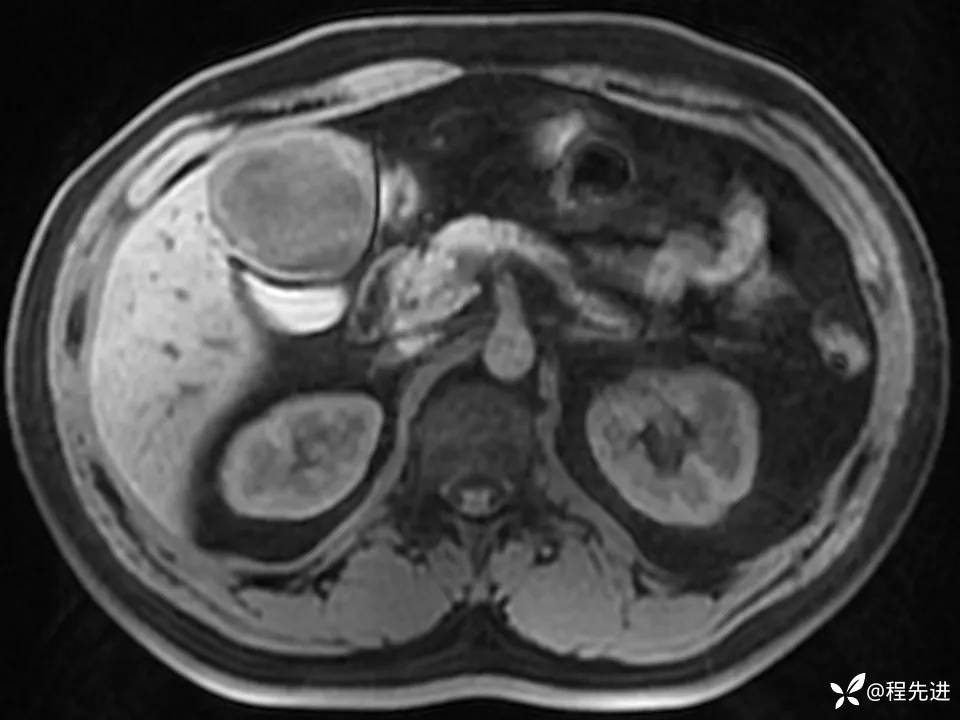

患者性别:男

患者年龄:27岁

简要病史:体检发现肝脏占位2周

既往史:平素体健,无特殊

实验室检查:(-)